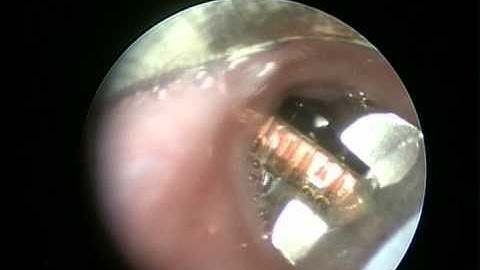

Endoscopic removal of coin with help of Roth Net under GA